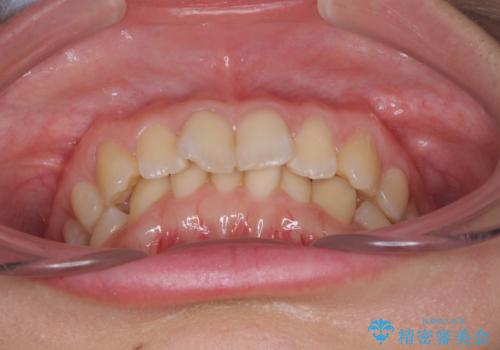

インビザラインによる前歯の矯正治療

- 口元の深い咬み合わせ(ディープバイト)を気にして来院された患者様です。

インビザラインによる上下歯列の遠心移動(後方移動)により、口元のデコボコとディープバイトを改善することとしました。

下顎左右の犬歯とその後ろにある第一小臼歯、計4歯がシミュレーション通りに動かずディープバイトがなかなか改善されませんでした。

マウスピースの再製作を何度か行いましたがうまくいかないため、部分的にワイヤー矯正を併用することを提案しました。しかし、最も気になっていた前歯のデコボコはきれいに改善されたため、これ以上治療を希望されず、治療を終了することとしました。(今後気になった際には再開する予定です)